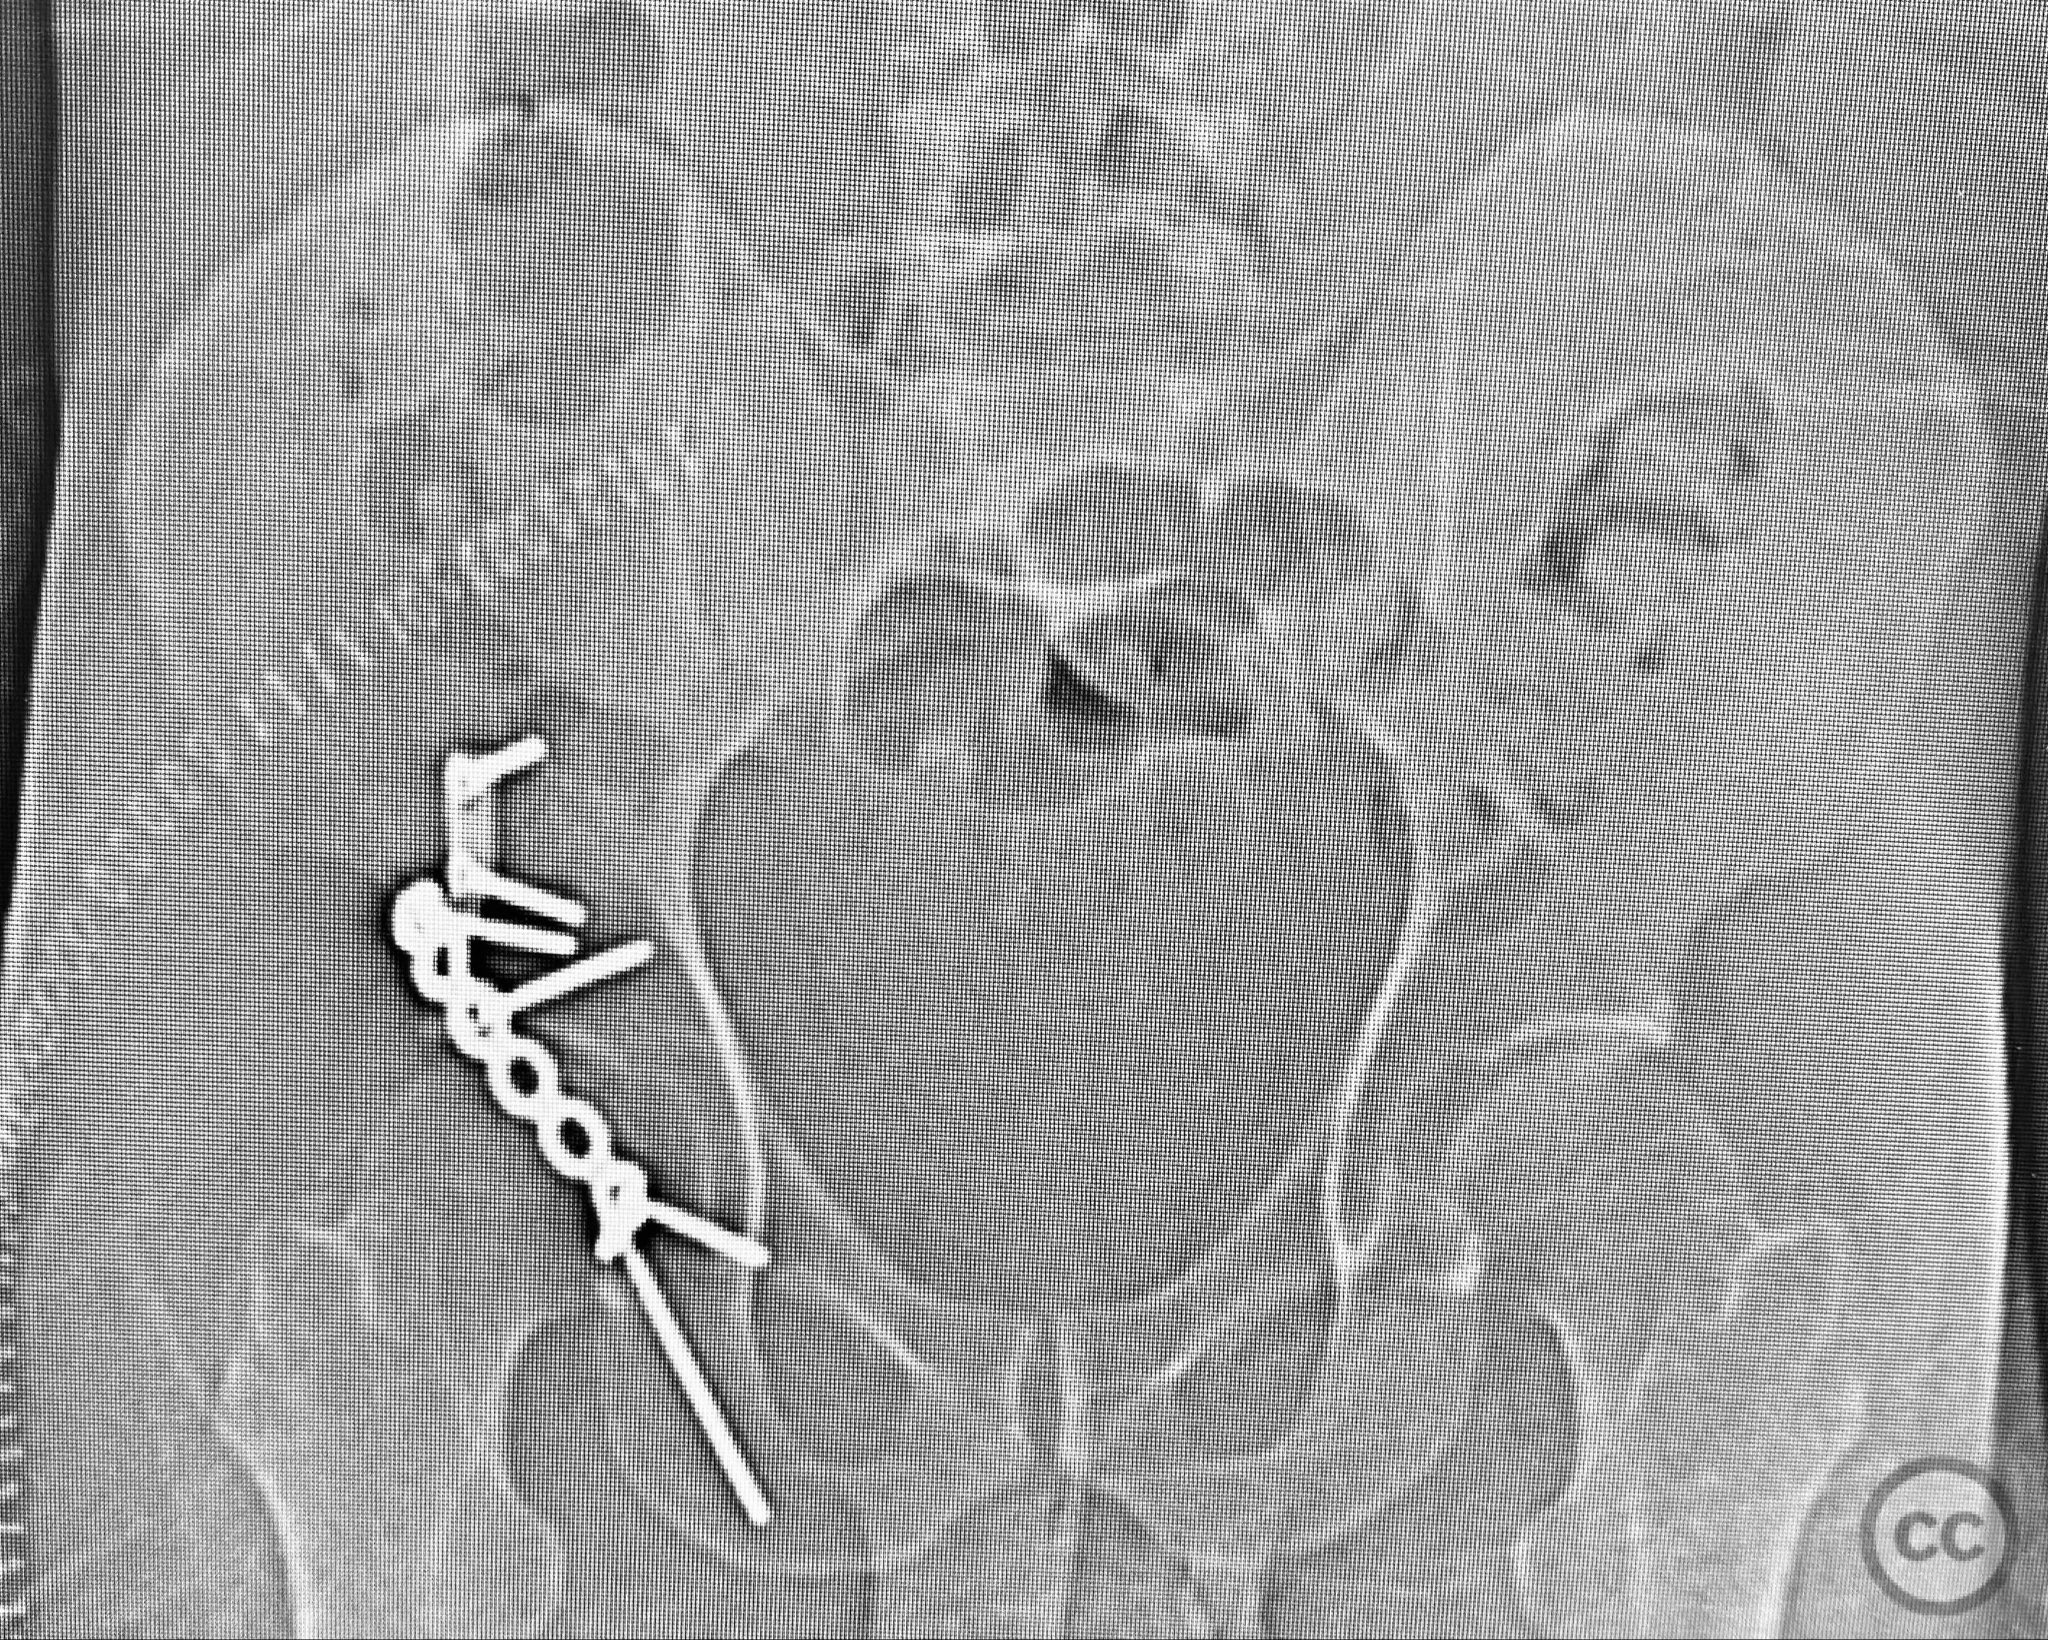

Clinical and radiological findings:  A middle-aged patient sustained a posterior wall acetabular fracture-dislocation, as demonstrated on initial AP pelvic radiograph. The film revealed a sizeable posterior wall fragment, cranial lateral impaction of the acetabular dome, and subtle deformation of the femoral head contour. Neurovascular examination was performed, including assessment of distal pulses and sciatic nerve function. The ipsilateral knee and anterior chest were examined for associated injuries (including possible knee ligamentous injury and thoracic trauma). An initial attempt at closed reduction under sedation was unsuccessful.

Planning remarks:  The preoperative plan included advanced imaging with CT, including 3D surface renderings, to further delineate the extent of articular impaction, wall fragment size, and comminution. The plan was for open reduction and internal fixation via a posterior Kocher-Langenbeck approach in the prone position. Elevation of impacted articular segments was planned, with structural support using autologous bone graft harvested from the greater trochanter. Fragment-specific fixation was planned with a spring hook plate for the cranial wall fragment and a reconstruction plate for the main posterior wall fragment.